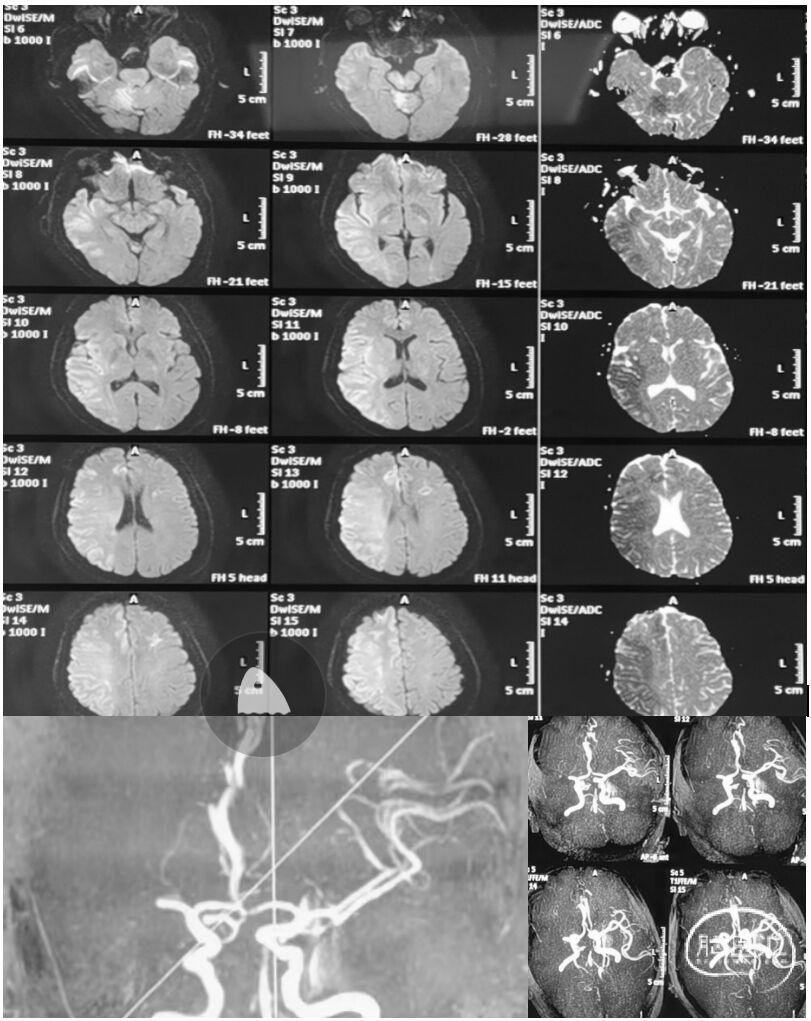

辅助检查:头颅MRI+MRA示:双侧小脑半球、右侧大脑半球多发急性期脑梗塞,右侧大脑中动脉重度狭窄或闭塞改变。

DSA提示:右侧大脑中动脉M1段以远闭塞,右侧大脑前动脉皮层支少量代偿,右侧大脑前动脉A3段血栓影,远端流速可,基底动脉尖端未见显影,考虑急性闭塞。